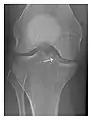

Occult osseous injuries may result from a direct blow to the bone by compressive forces of adjacent bones against one another or by traction forces during an avulsion injury. Lesions in the tibial plateau, hip, ankle, and wrist are often missed. In a tibial plateau fracture, any disruption of the posterior and anterior cortical rims of the plateau should be sought. Impaction of subchondral bone will appear as an increased sclerosis of the subchondral bone (Figure 1). In the hip, posterior acetabular fractures also present subtle radiographic findings. The acetabular lines should then be carefully examined keeping in mind that the posterior rim, which is harder to see on X-rays, is more frequently fractured than the anterior rim (Figure 2). In the wrist, detection of carpal bone fractures is often challenging, with up to 18% of scaphoid fractures radiographically occult. Carpal fractures, especially the scaphoid, are associated with the risk of avascular necrosis. In apparently normal wrist radiographs from symptomatic patients, if there is history of a fall on an outstretched hand with pain in the anatomic snuffbox, suggesting scaphoid injury, the initial examination with posteroanterior, lateral, and pronation oblique views must be complemented by other specific views such as supination oblique and the "scaphoid" view A careful examination of cortices for evidence of discontinuity or offset and cancellous bone for lucency is necessary (Figure 3).[1]

Figure 1: A 56-year-old woman presenting with left knee pain after a fall. (a) Initial anteroposterior radiograph was considered normal, however, subtle cortical disruption of the anterior rim of the medial tibial plateau, medial to the tibial spine, is noted (arrow). (b) Coronal T1-weighted MRI confirms the cortical disruption (arrow) and shows extensive fracture through the proximal tibia. (c) Coronal proton density-weighted image with fat saturation shows extensive edema in the subchondral bone. Note also hypersignal adjacent to the medial collateral ligament corresponding to a grade I sprain (arrowheads).[1]